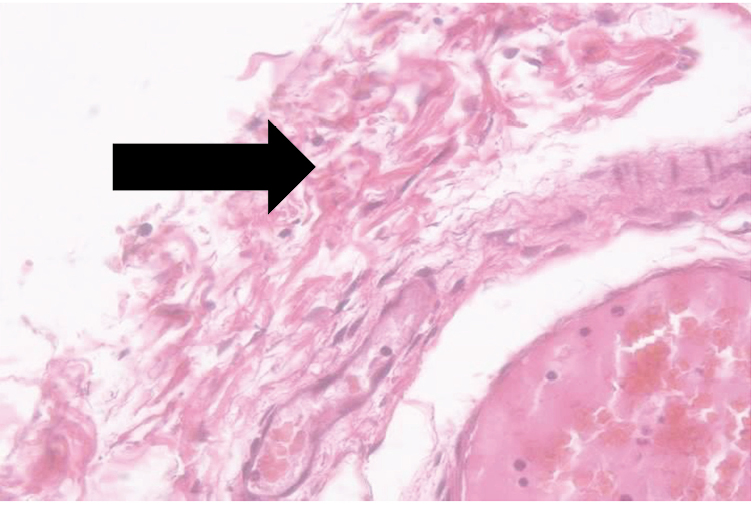

При гистологическом исследовании микропрепаратов свиней контрольной группы отмечались значительные повреждения мезотелия, покрывающего серозную оболочку кишки свиньи: тотальное разрушение слоя, формирование фибриновых пленок на поверхности серозной оболочки и дезорганизация оболочек кишки, присутствие фибробластов вплоть до подслизистой основы. Изменения наблюдались также в сосудистом русле, тканевых элементах серозной оболочки и подслизистой основы в виде набухания эндотелиоцитов, резкого полнокровия сосудов и разволокнения подслизистой основы за счет отека (рис. 8).

Рис. 8. Микропрепарат кишки свиньи контрольной группы. Дезорганизация серозной и мышечной оболочек. Окраска: гематоксилин и эозин. Ув. ×400 / Fig. 8. Control group pig intestine micropreparation. Disorganization of the serous and muscular membranes. Staining: hematoxylin and eosin. Mag. ×400